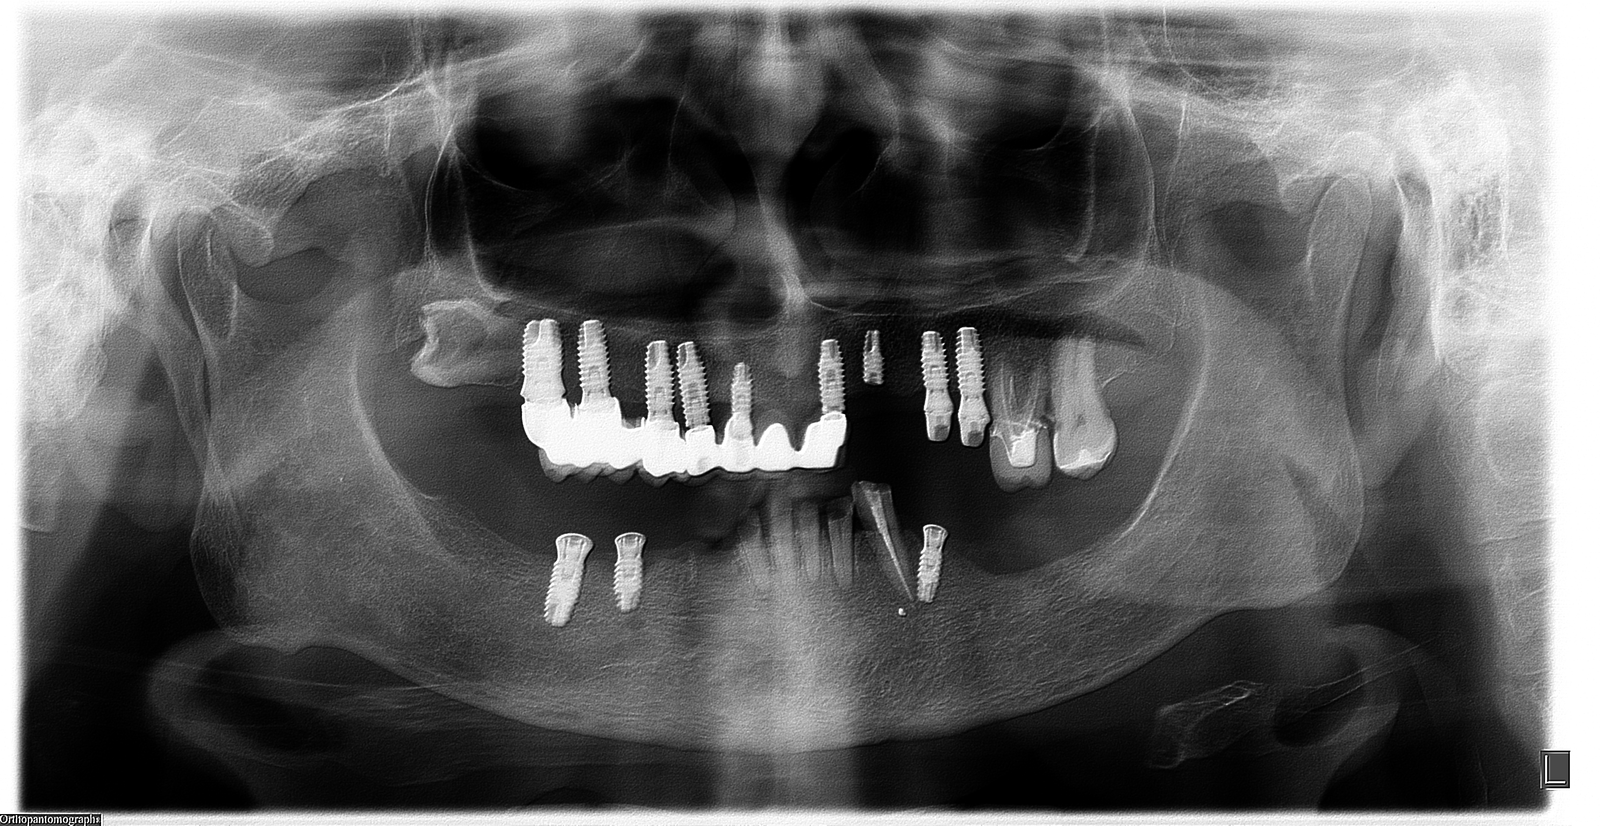

SOS con los Implantes inferiores!!

Buenos días detectives! Me podeis echar una mano con los implantes inferiores de este paciente? Se los pusieron hace muuuuuchos años impactándolos. Muchas gracias de antemano!